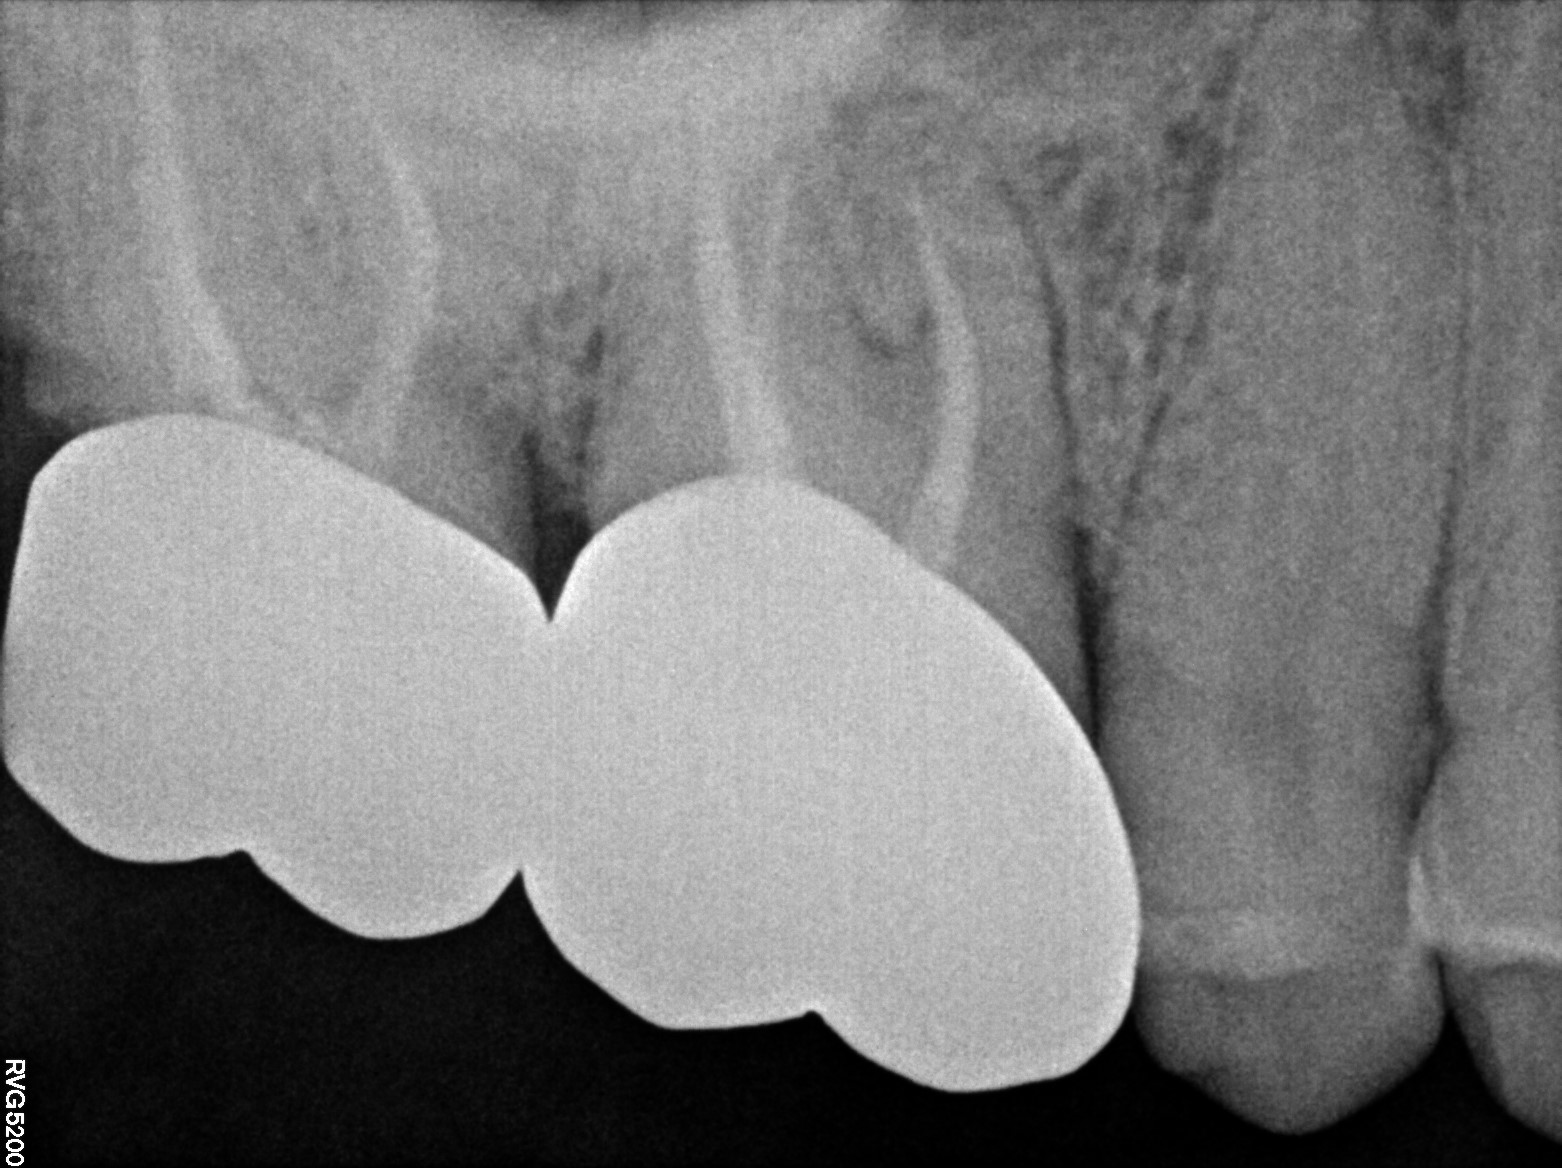

Dental Radiographs FHIR: DocumentReference · LOINC 24641-7

R55.jpg

24641-7